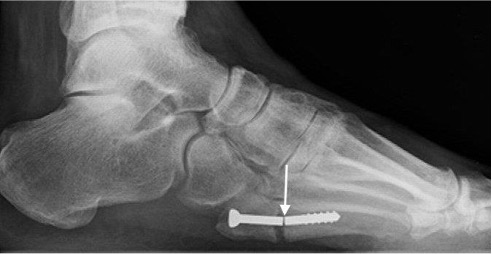

Screw fracture (arrow)

Avascular necrosis of the alar dome following talar neck fracture with subchondral sclerosis and fracture (arrows). Note disuse osteopaenia.